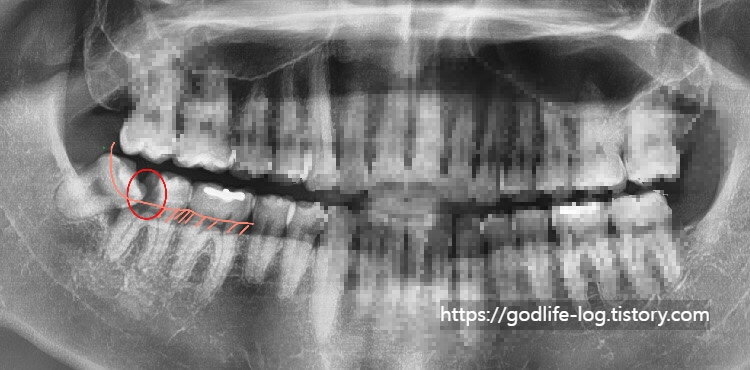

위 사진과 같이 주로 아래쪽에 있는 사랑니는 수평으로 매복되어 있는 경우가 많습니다. x-ray사진상으로는 치아가 잘 보이지만 실제 구강 내에서는 사랑니의 일부분만 보입니다. 맨 끝에 있는 어금니와 사랑니 사이에 음식물이 끼면 음식물이 잘 안 빠지고 그것 때문에 잇몸에 염증이 생기면서 잇몸이 붓고 피가 나고 정말 심한 경우에는 입을벌리기 힘든경우까지 생길 수 있습니다. 또 이런게 반복되면서 사랑니가 아닌 제2대구치라고 불리는 어금니에 영향을 주게됩니다. 위 사진과같이 충치가 심하게 생길수도있고 염증이 생기면서 사랑니와 어금니 사이에 있는 잇몸뼈를 소실되게 할수도 있습니다.이렇게 문제가 생기는 경우엔 사랑니를 발치가 필요합니다. 사랑니때문에 한번 염증이 생기면 계속 염증이 생기고, 앞치아에 안좋은 영향을 줄 수 있습니다.

위 사진 또한 사랑니 때문에 어금니에 충치가 생긴 모습인데요, 분홍색 선으로 표시해 놓은 곳이 실제 우리 눈에 보이는 잇몸 부분이고 아래쪽으로는 잇몸에 덮여있어서 보이지 않는 곳입니다. 충치가 잇몸 안쪽에 안 보이는 부분까지 깊이 생겨서 이런 경우에는 사랑니를 발치한다고 해도 어금니를 충치치료해서 살리기가 어렵습니다

사람의 아래턱에는 아랫입술까지 이어지는 커다란 신경관이 하나 지나가는데요, 바로 사진에서 빨간색으로 표시해 놓은 부분입니다. 아무래도 사랑니를 발치하는 과정에서 신경관이 가까울 경우 신경을 건드릴 수 있는데 이런 경우에 신경관에 손상이 올 수 있습니다. 증상은 마취가 풀릴 시간이 지났음에도 불구하고 계속 얼얼한 느낌, 저린 느낌이 남아있습니다.